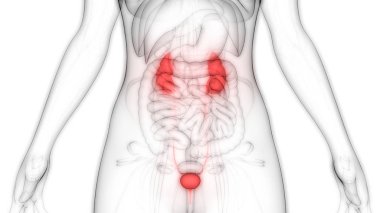

İdrar torbası anatomisi olan erkek idrar sistemi böbrekleri. 3d

ArkaplanGrafikselresimlemedizaynİzole edilmişkişiİnsaninsanlarSoyutSağlıksağlıklıİlaçerkekTıbbifasulyesiluetPankartgövdeHastalıkİçeridebiyolojiBilimkanserSistemAcıorgKasİskeletanatomiKas gücüx ışınıfizyolojiBöbrekTümöranatomikİdrar torbasıÜreterİdrarProstatÜretraÜrolojibilgi grafiği3B illüstrasyonnefronProstat bezinefrolojiBenzer İçerikler